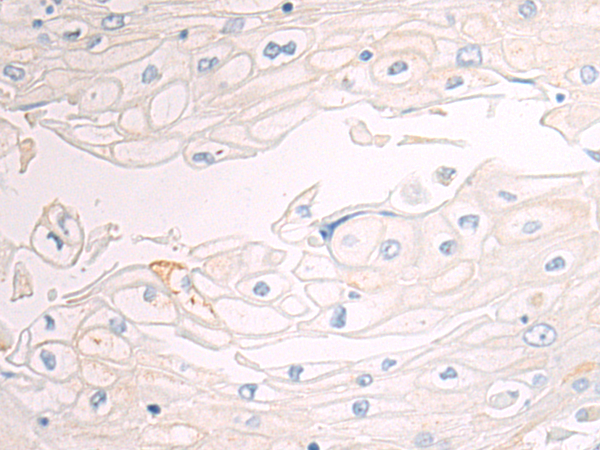

Product Image

| Gel: 12%SDS-PAGE, Lysate: 40 μg, Lane: A172 cell lysate, Primary antibody: TD-P05527(CD70 Antibody) at dilution 1/650, Secondary antibody: Goat anti rabbit IgG at 1/5000 dilution, Exposure time: 30 seconds | The image is immunohistochemistry of paraffin-embedded Human esophagus cancer tissue using TD-P05527(CD70 Antibody) at dilution 1/50. (Original magnification: ×200) |